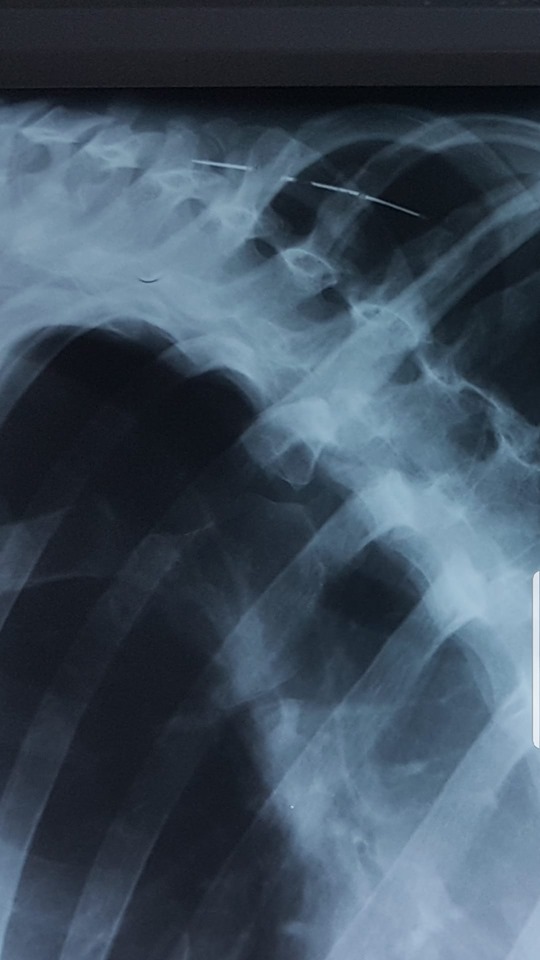

Un bărbat din județul Botoșani a ajuns la spital cu mai multe ace înfipte în tot corpul. El a ajuns pe mâna unui medic de la Secția din Săveni a Spitalului Județean Botoșani, care a rămas uimit când a văzut ce se află în corpul bărbatului.

„Ce se mai poate găsi în corpul unui pacient. Ace, cuie, sarme. In 40 de ani de când mă învârt în ale medicinii nu am mai vazut asa ceva. Ca o precizare este vorba de un pacient cu tulburări afective si psihice. Acele sunt de mult acolo, umăr, gât, axila. Corpul le acceptă. Ce sa facă, săracul. Este o victimă”, a spus medicul Elena Cardaș.